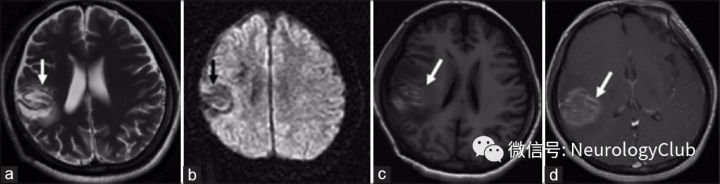

根据神经影像学形态特征,可以将TDLs的病灶分为三类(图1-7):(1)弥漫浸润性病灶:边界不清,不均匀强化,T2WI可见弥漫浸润性生长方式(图1a和b);(2)环形强化病灶:病灶为圆形或类圆形,呈闭环或开环强化(图1c);(3)巨大囊性病灶:T1WI低信号,T2WI高信号,边界清,环形强化(图1d)。

图1:三例TDLs患者,三种形态类型:浸润性(a和b),环形强化(c)和巨大囊性(d)

1. MRI平扫:TDLs病灶常为T1WI低信号,T2WI高信号,较CT显示的病灶范围大。约70-100%TDLs患者的病灶在T2WI上为高信号,边界清楚(图5b),而少数病灶的边缘可见T2WI低信号(图4a)。大多数TDLs病灶具有占位效应(图1a,2b,2c,和3a),但较脑肿瘤轻,病灶周围常可见水肿。在急性或亚急性期,水肿主要为细胞毒性水肿,DWI序列上为高信号(图4b)。经激素治疗后,病灶可在数周内变小或消失。

2. 增强MRI:在急性期或亚急性期,由于血脑屏障的破坏,增强MRI可见不同模式的强化,如结节状、闭环、开环或火焰状强化。开环强化又称为C形强化(图5a),是最典型的,即病灶边缘不连续的半环形强化。对于部分TDLs病灶,扩张的小静脉形成梳齿状结构(图1b和2d),垂直于侧脑室,常见于急性期或亚急性期,是TDLs相对特异的影像表现,而未见于脑肿瘤。